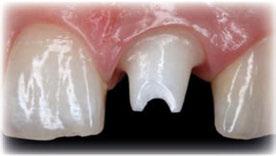

Guía canina

E-max CAD sobre implante

E-max CAD sobre diente natural

E-max CAD técnica “Cut-back”

E-max CAD “Monolítico”

E-max CAD “Monolítico” Pre

innovador Disilicato de Litio (LS2) del sistema de cerámica

IPS e.max CAD no solo ofrece una altísima estética que también es de 2,5 a 3 veces más resistente 360 que el resto de cerámicas de vidrio. Por ello, este material cubre todos los requerimientos estéticos y también representa una alternativa eficiente a las restauraciones unitarias ZrO2. (Zirconio)

El innovador Disilicato de Litio (LS2) del sistema de cerámica vítrea IPS e.max CAD no solo ofece una altísima estética sino que también es de 2,5 a 3 veces más resistente 360 MPa que el resto de cerámicas de vidrio. Por ello, este material cubre todos los requerimientos estéticos y también representa una alternativa eficiente a las restauraciones unitarias de Zr02 (Zirconio).

El innovador Disilicato de Litio (LS2) del sistema de cerámica vítrea IPS e.max CAD no solo ofrece una altísima estética sino que también es de 2,5 a 3 veces más resistente 360 MPa que el resto de cerámicas de vidrio. Por ello, este material cubre todos los requerimientos estéticos y también representa una alternativa eficiente a las restauraciones unitarias de ZrO2. (Zirconio)

IPS e.max está avalado por la experiencia clínica que ha demostrado durante años, tanto en estética como en resistencia. La amplitud de elección del material, según el caso, en conjunción con la técnica empleada en nuestro laboratorio dotarán a los trabajos de la mayor estética para sus pacientes.